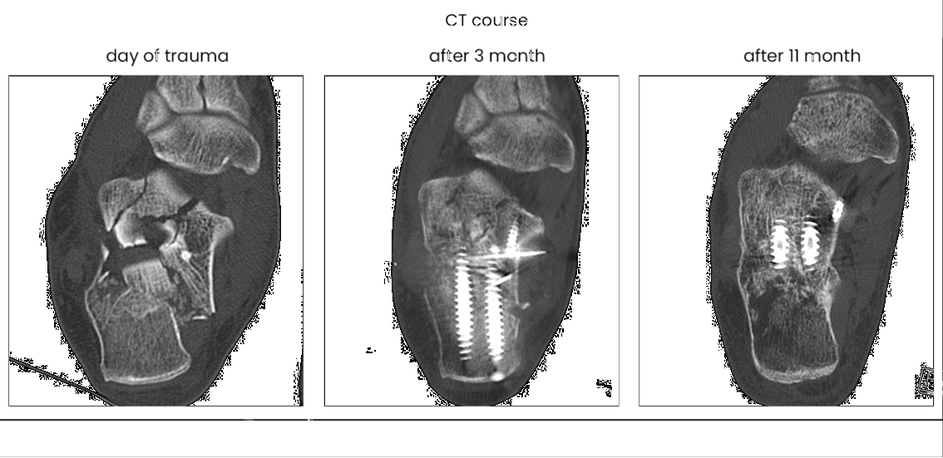

case 17BD, 47 years old, male, fall during work, 2 meters, "comminuted fracture", surgery after 2 days